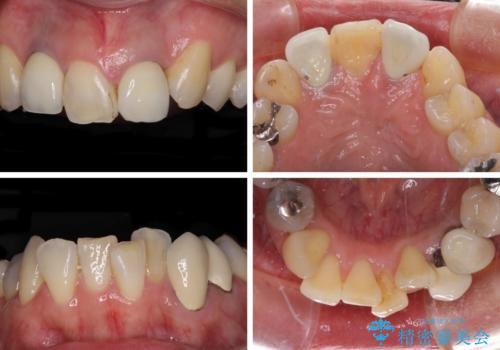

- 非対称な前歯や奥歯の目立つ銀歯を気にして来院された患者様です。

左上前から2番目の歯は、以前裏側に位置していたことから抜歯をされていましたが、前歯の非対称が長年気になっているとのことでした。

矯正治療によって前歯にスペースを作り、左右対称となるようにオールセラミッククラウンにて補綴治療を行うとしました。

他にも奥歯の咬み合わせに問題があったので、全顎的な矯正治療を行い、前歯以外にも口を開けたときに目立つ奥の銀歯をセラミッククラウンにて補綴治療を行うこととしました。